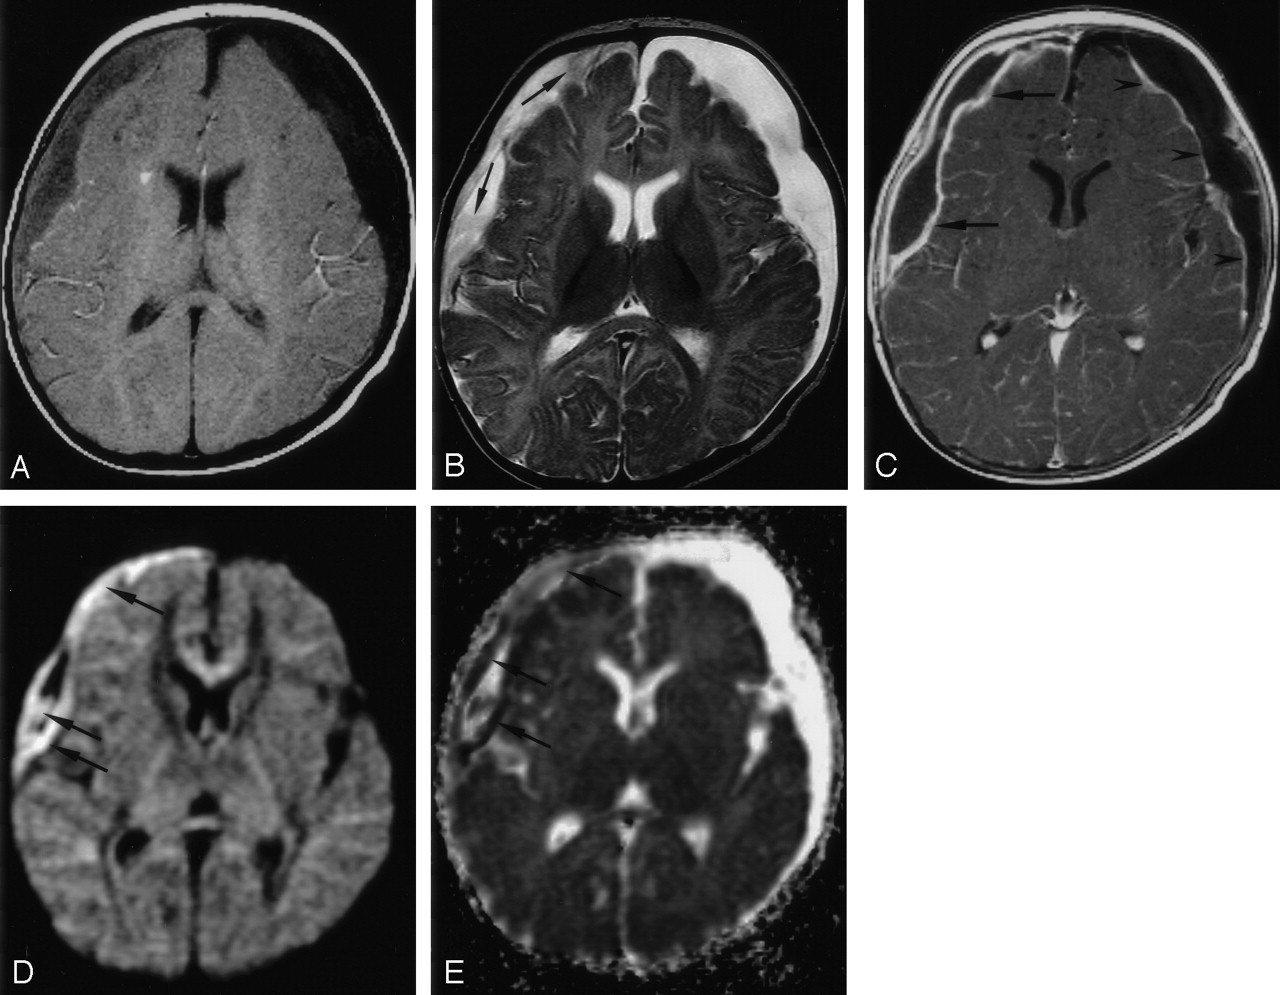

All 10 patients had reduced water diffusion in their SDE (Table 2). On DWIs, SDE showed high signal intensity in nine patients (90%) (Fig 1) and mixed hyperintensity and hypointensity in one (Fig 2). The mean ADC value of the seven SDE was 0.604 ± 0.18 mm2/s (mean ± SD) and lower than that of normal cortical gray matter (1.029 ± 0.175 mm2/s; P = .001). On T1WIs, the SDE were isointense in five patients (50%) (Fig 1), mildly hypointense in one (10%), and hypointense in four (40%) (Fig 2). On T2WIs, they were hyperintense in five patients (50%) (Fig 2), mildly hyperintense in four (40%), and isointense in one (10%) (Fig 1). Postcontrast T1WI showed smooth, linear, capsular enhancement in nine patients (90%) with SDEs (Fig 1) and irregular capsular enhancement in one (10%). The SDE showed mass effect on brain parenchyma in eight patients (80%).

Patient 1. Right SDE and left RSE.

A, Axial T1WI (650/14) shows intermediate signal intensity in the right SDE and hypointensity in the left RSE.

B, Axial T2WI (6000/99) shows high signal intensity in both subdural collections. Strands of intermediate signal intensity (arrows) are noted in the right SDE.

C, Axial contrast-enhanced T1WI (800/20) with MT shows peripheral enhancement of both subdural collections. The enhancement is thicker in the right SDE (arrows) than in the left RSE (arrowheads).

D, Axial DWI (4000/110, b = 1000 s/mm2) shows mixed high (arrows) and low signal intensities in the right SDE.

E, Corresponding ADC map shows mixed low (arrows) and high signal intensities in the right SDE, indicating heterogeneous water motion. Increased water motion is noted in the left RSE.